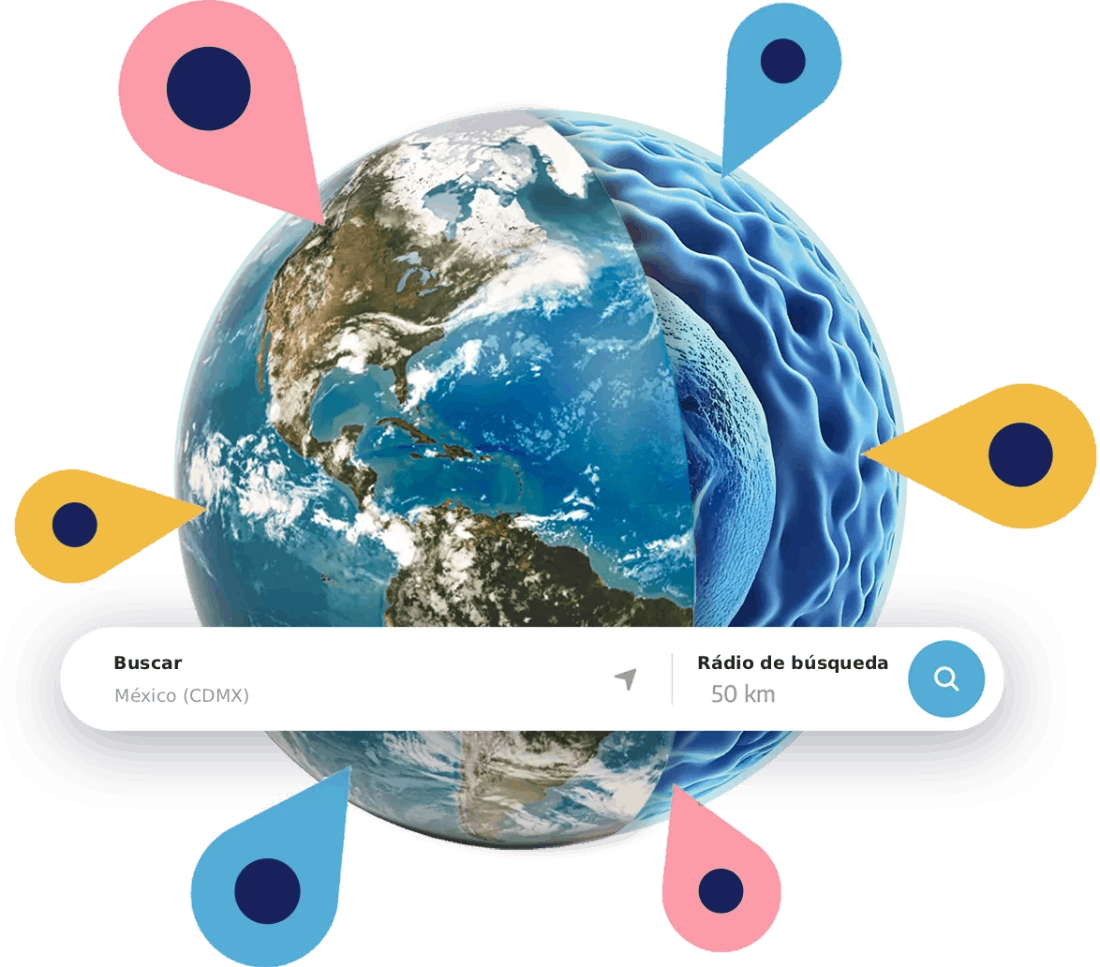

Centros de tratamiento MBST®

MBST® es una terapia de uso clínico, aplicada por profesionales de la salud. Su fabricación certificada por TÜV respalda estándares de calidad, seguridad y confiabilidad a nivel internacional.

¿Te gustaría saber si puede ser adecuada para tu caso y dónde podrás acceder a ella en México? Escríbenos y te compartimos la información disponible.

Actualmente nos encontramos en fase de implementación tecnológica. Aunque aún no ofrecemos sesiones activas, estamos integrando una comunidad de pacientes interesados en alternativas no invasivas para la salud musculoesquelética.

- Agwa Bosques Corporativo Torre 3 piso 44, Carr. México-Toluca 1535, Cooperativa Palo Alto, Cuajimalpa de Morelos, 05110, CDMX

- +52 56 4335 1639

- contacto@mbstmexico.mx